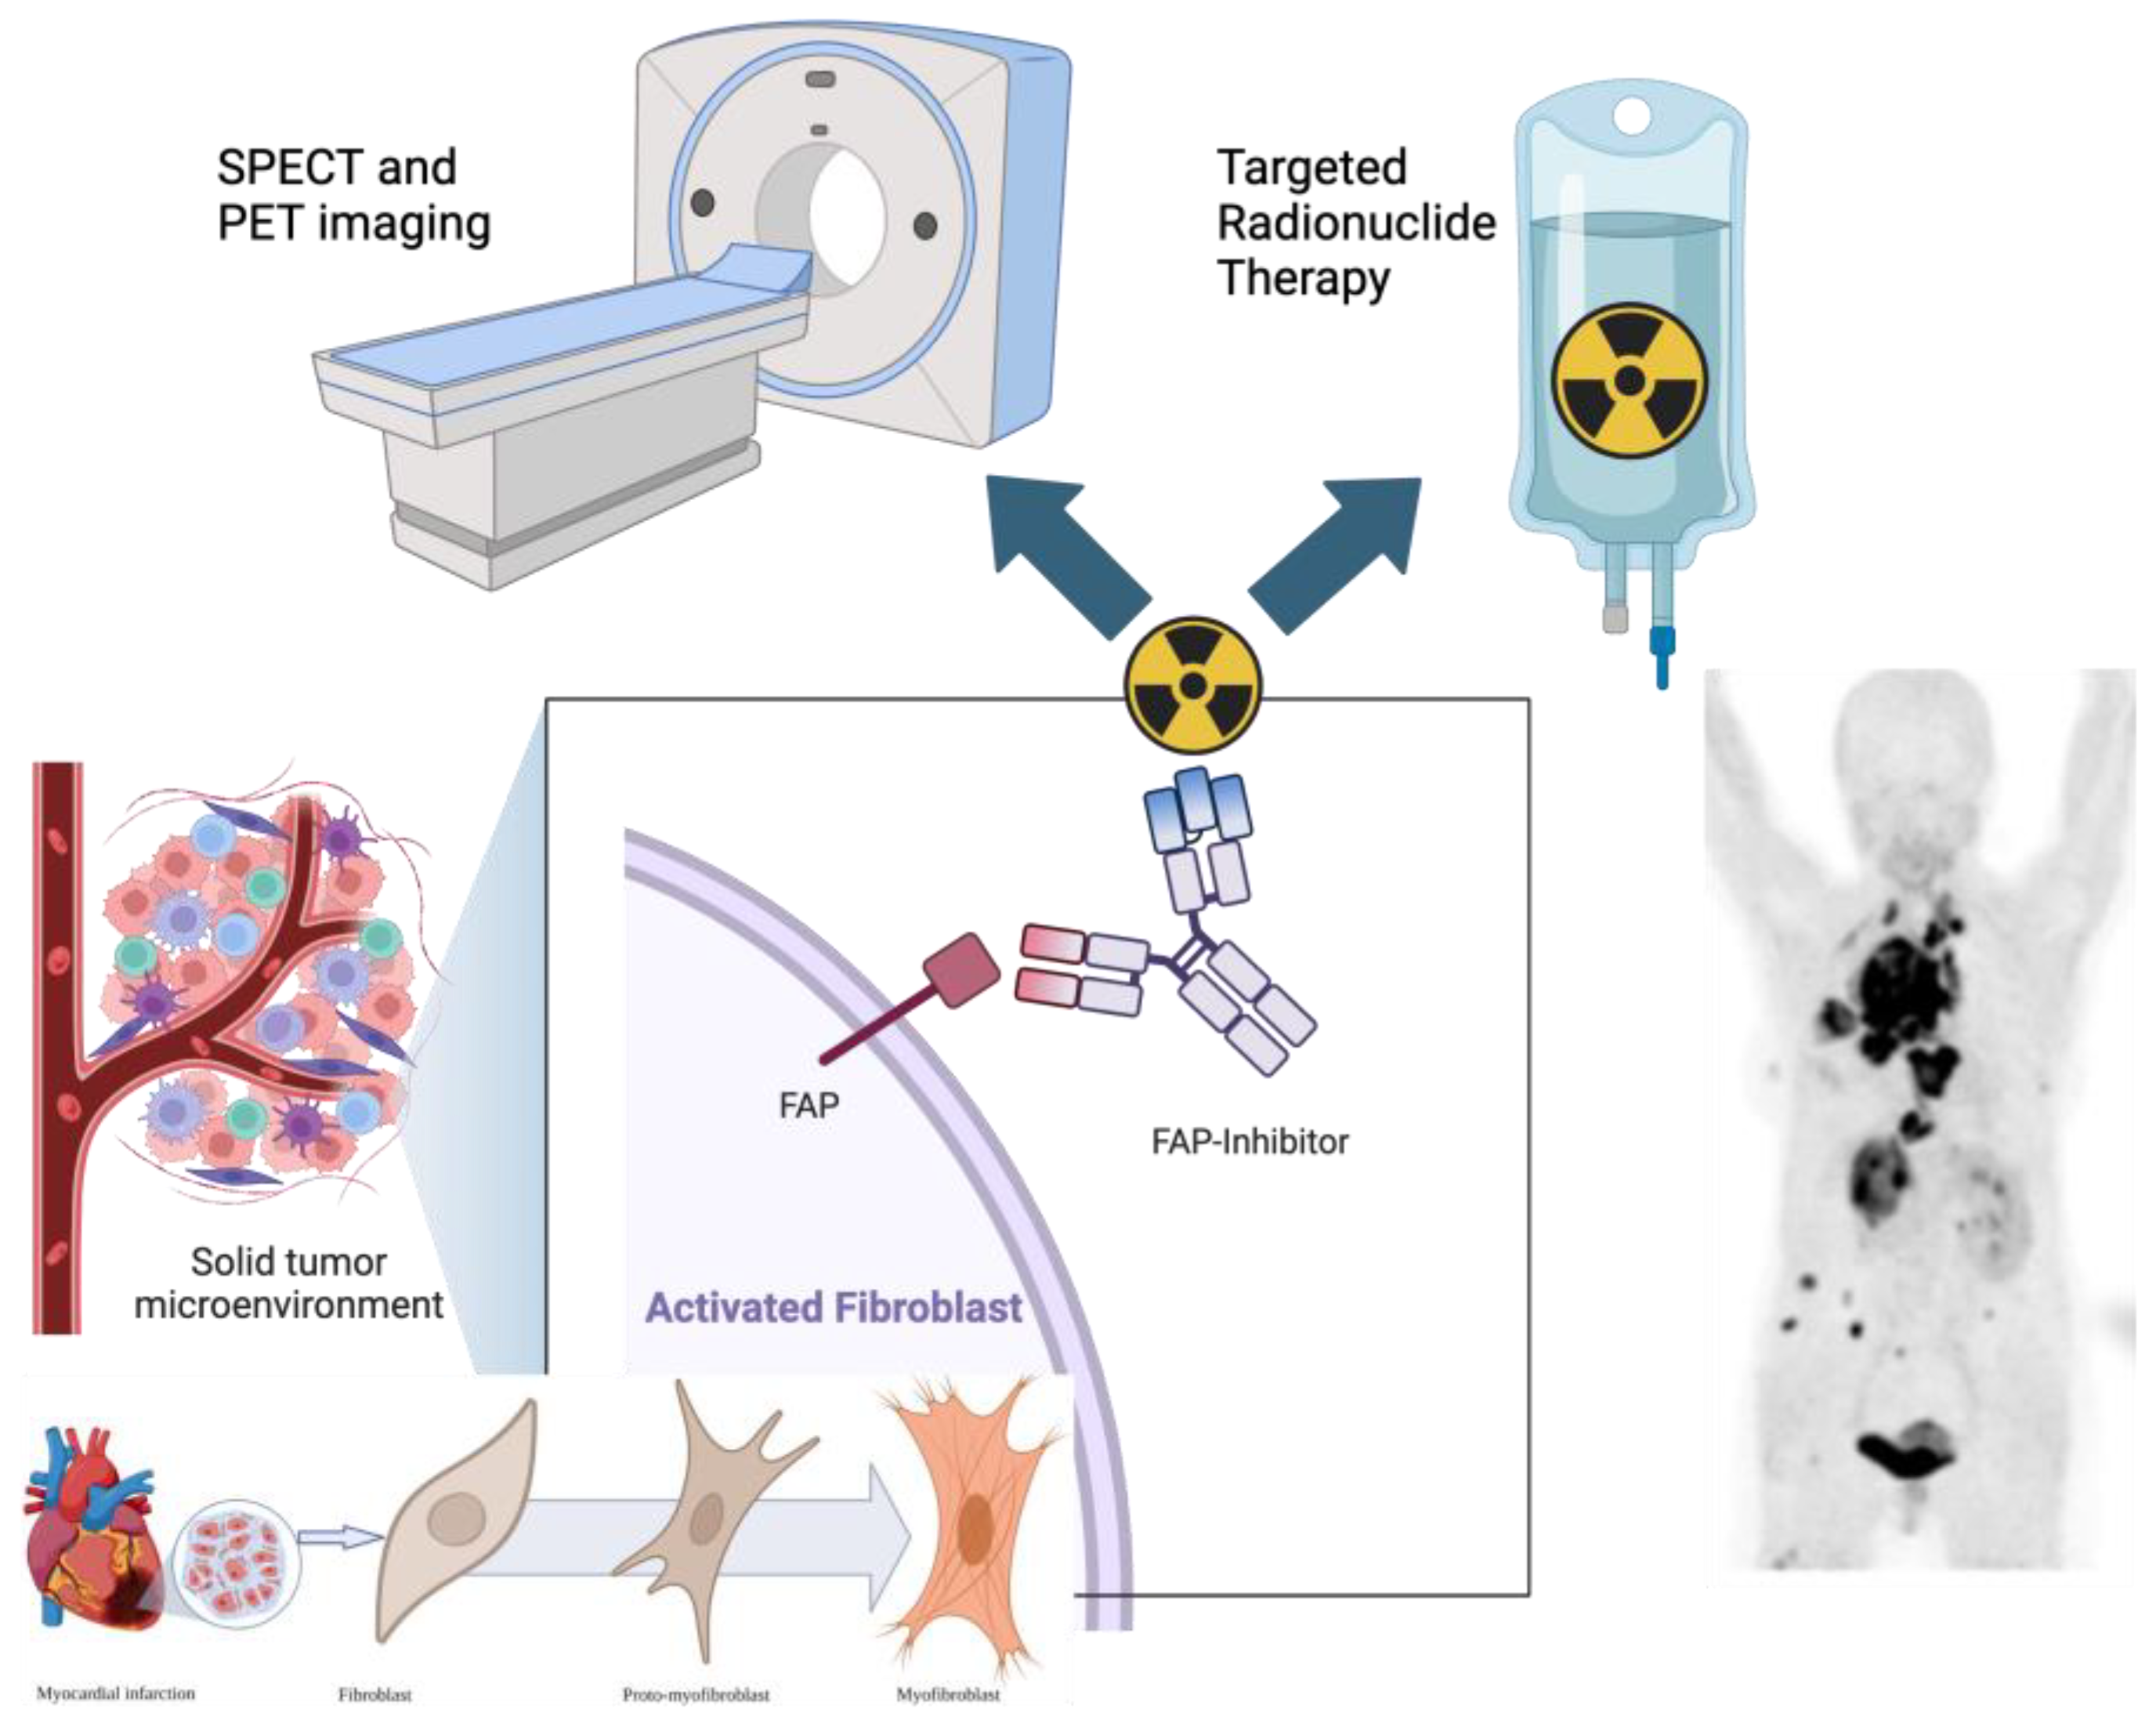

1. Introduction to FAPI Theranostics

FAPI-Based Radioligands

5. FAPI PET in Cardiovascular Disease

10. FAPI-Based Theranostic Approaches